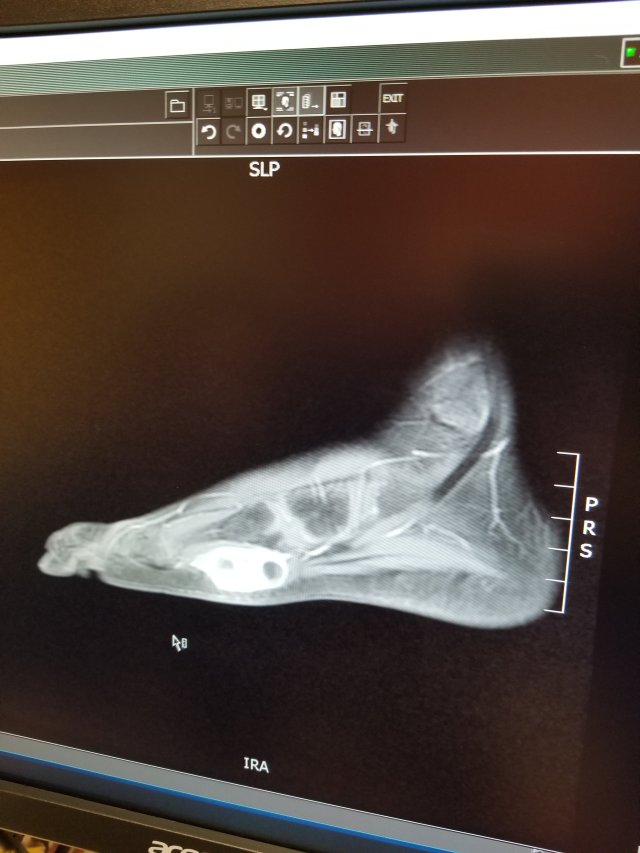

We met with Eli’s surgeon yesterday to discuss the foot tumor resection. He showed us scans from November

And one from a couple weeks ago:

The white blob between the 4th & 5th metatarsals is the tumor. Chemo has done a good job of shrinking it. Yay!